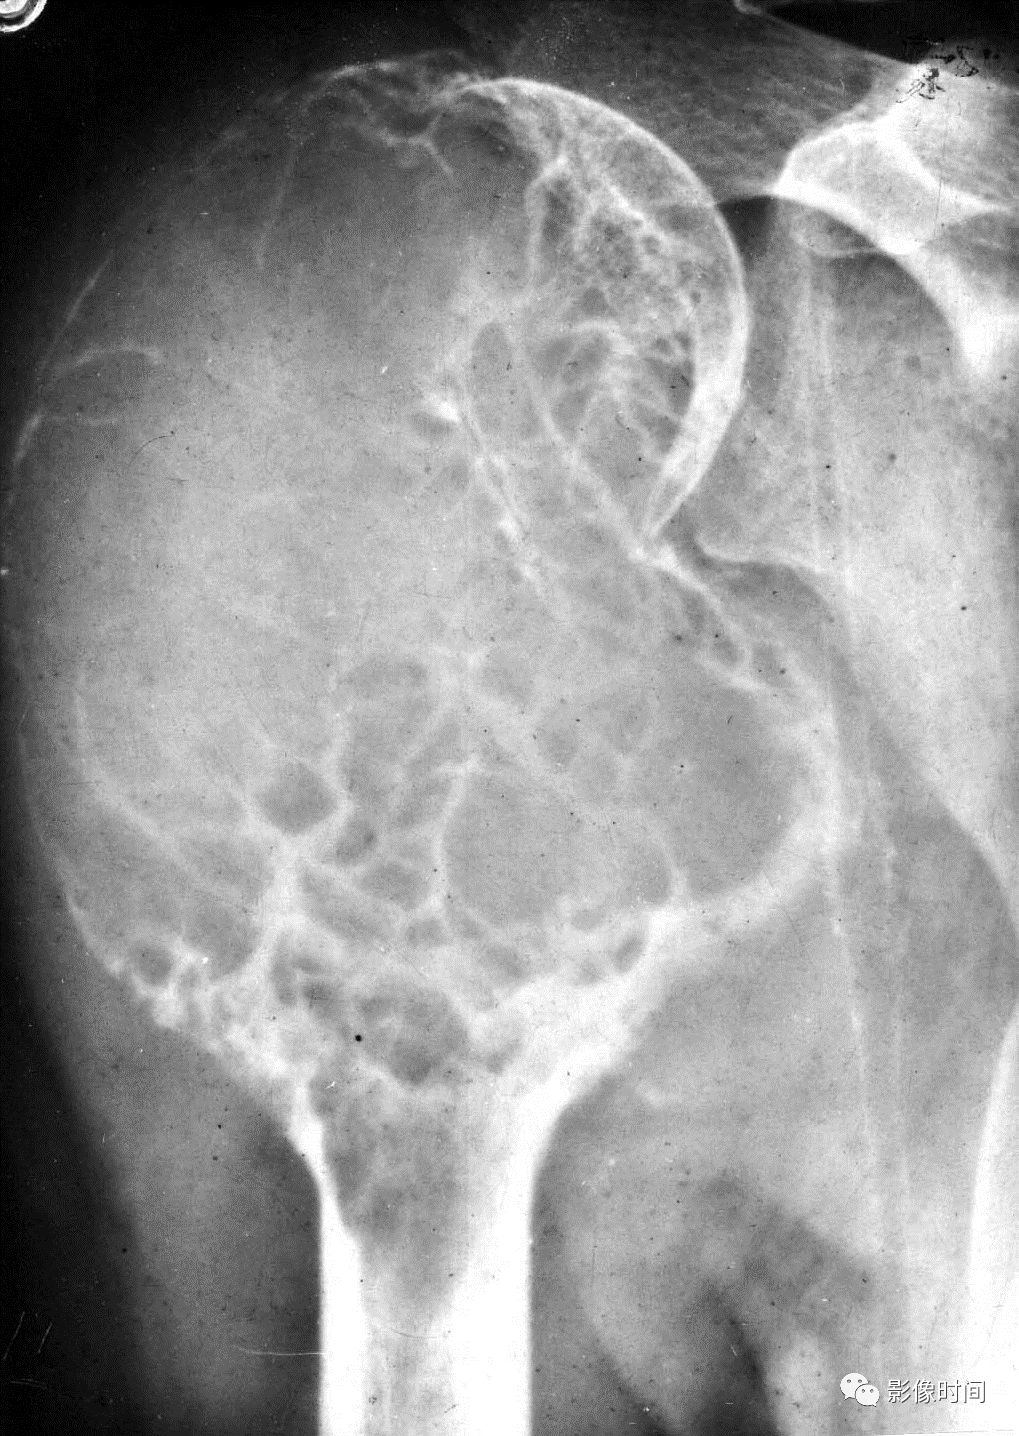

(二)膨胀性破坏  膨胀性破坏是地图样破坏的特殊形式,影像学表现为骨质破坏区骨膨胀,周围可见不同程度扩张的骨壳(图 5、图 6、图 7、图 8)。

膨胀性破坏是由于肿瘤从骨皮质内面破坏,骨外膜增生形成新生骨造成膨胀的。

引起膨胀性破坏见于大多数良性肿瘤和肿瘤样病变如单纯性骨囊肿,动脉瘤样骨囊肿、内生软骨瘤和软骨粘液纤维瘤等,少数也可见于恶性肿瘤如转移瘤、骨髓瘤等。

图 6  膨胀性破坏:骨巨细胞瘤